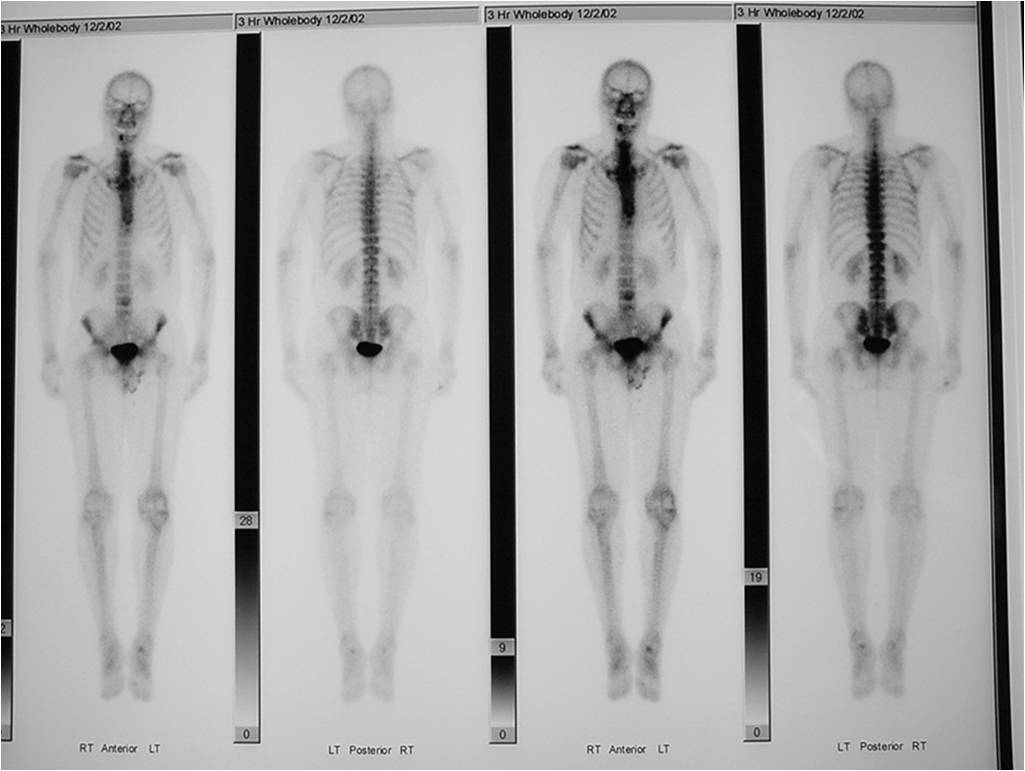

- Bone Scan: Lesion that is hotter than ASIS